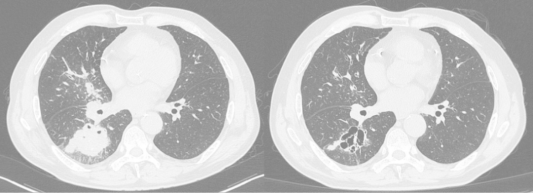

完成两周期治疗后,苗先生病情有了显著好转。胸部CT显示肺部肿瘤明显缩小,实性部分基本消失变成了多房空洞;最大的转移淋巴结从2.3cm缩小到1.5cm;之前升高的肿瘤标志物中多项已恢复正常。咳嗽、胸闷等症状明显减轻,生活质量大大提高。目前,苗先生正按计划继续随访治疗。